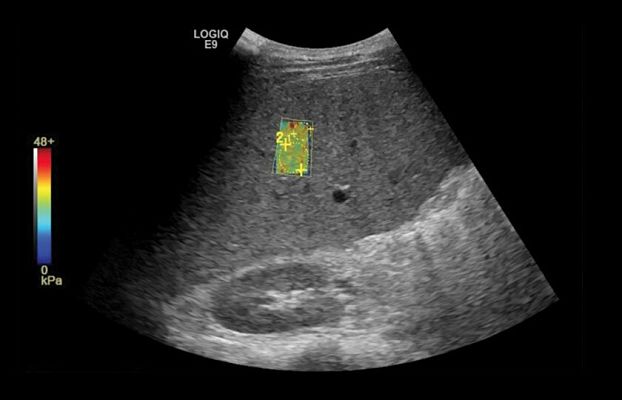

Клинические изображения

- Strain Elastography - программа эластографии.

- Elastography Q-analysis + CF/PDI Quantification - программа количественного анализа для эластографии и анализа васкуляризации в режиме ЦДК и ЭД.

- Shear Wave Elastography - режим эластографии сдвиговой волны. Поддерживается датчиками C1-6-D, C1-6VN-D и 9L-D.

- Эластография сдвиговой волны и компрессионная эластография — технологии неинвазивной оценки упругости тканей.